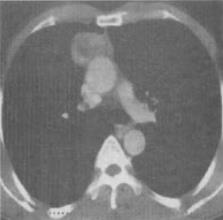

男,45岁,眼睑上抬困难3个月,CT检查如图。最可能的CT诊断为()。

A、畸胎瘤

B、神经纤维瘤

C、胸腺瘤

D、淋巴结增生

E、纵隔型肺癌

正确答案:

C